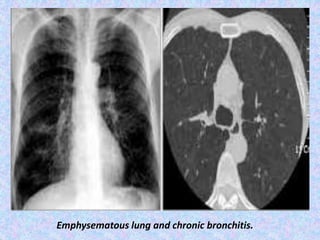

Emphysematous lung and chronic bronchitis.

CT in chronic bronchitis, bronchial wall thickening may be seen in

addition to enlarged vessels. Repeated inflammation can lead to

scarring with brochovascular irregularity and fibrosis.

Chronic bronchitis and the lines that leave the right hilum

horizontally show irregular borders because of chronic inflammation